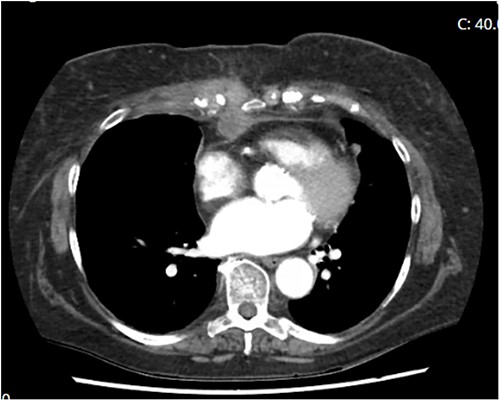

Although antimicrobials play a large role in the eradication of bacterial pathogens, antifungal therapies are not as contributory to the eradication of fungal infections [4]. Aggressive debridement (including sternectomy and excision of costal cartilages) was performed with the assistance of plastic surgery teams (Fig. 3). In early December 2021—after 10 surgical debridement surgeries—clean margins and negative cultures were obtained. The wound bed was deemed suitable for reconstructive surgery with omental flap and skin graft.

Sternectomy and costochondrectomy required for pathogenic clearance.